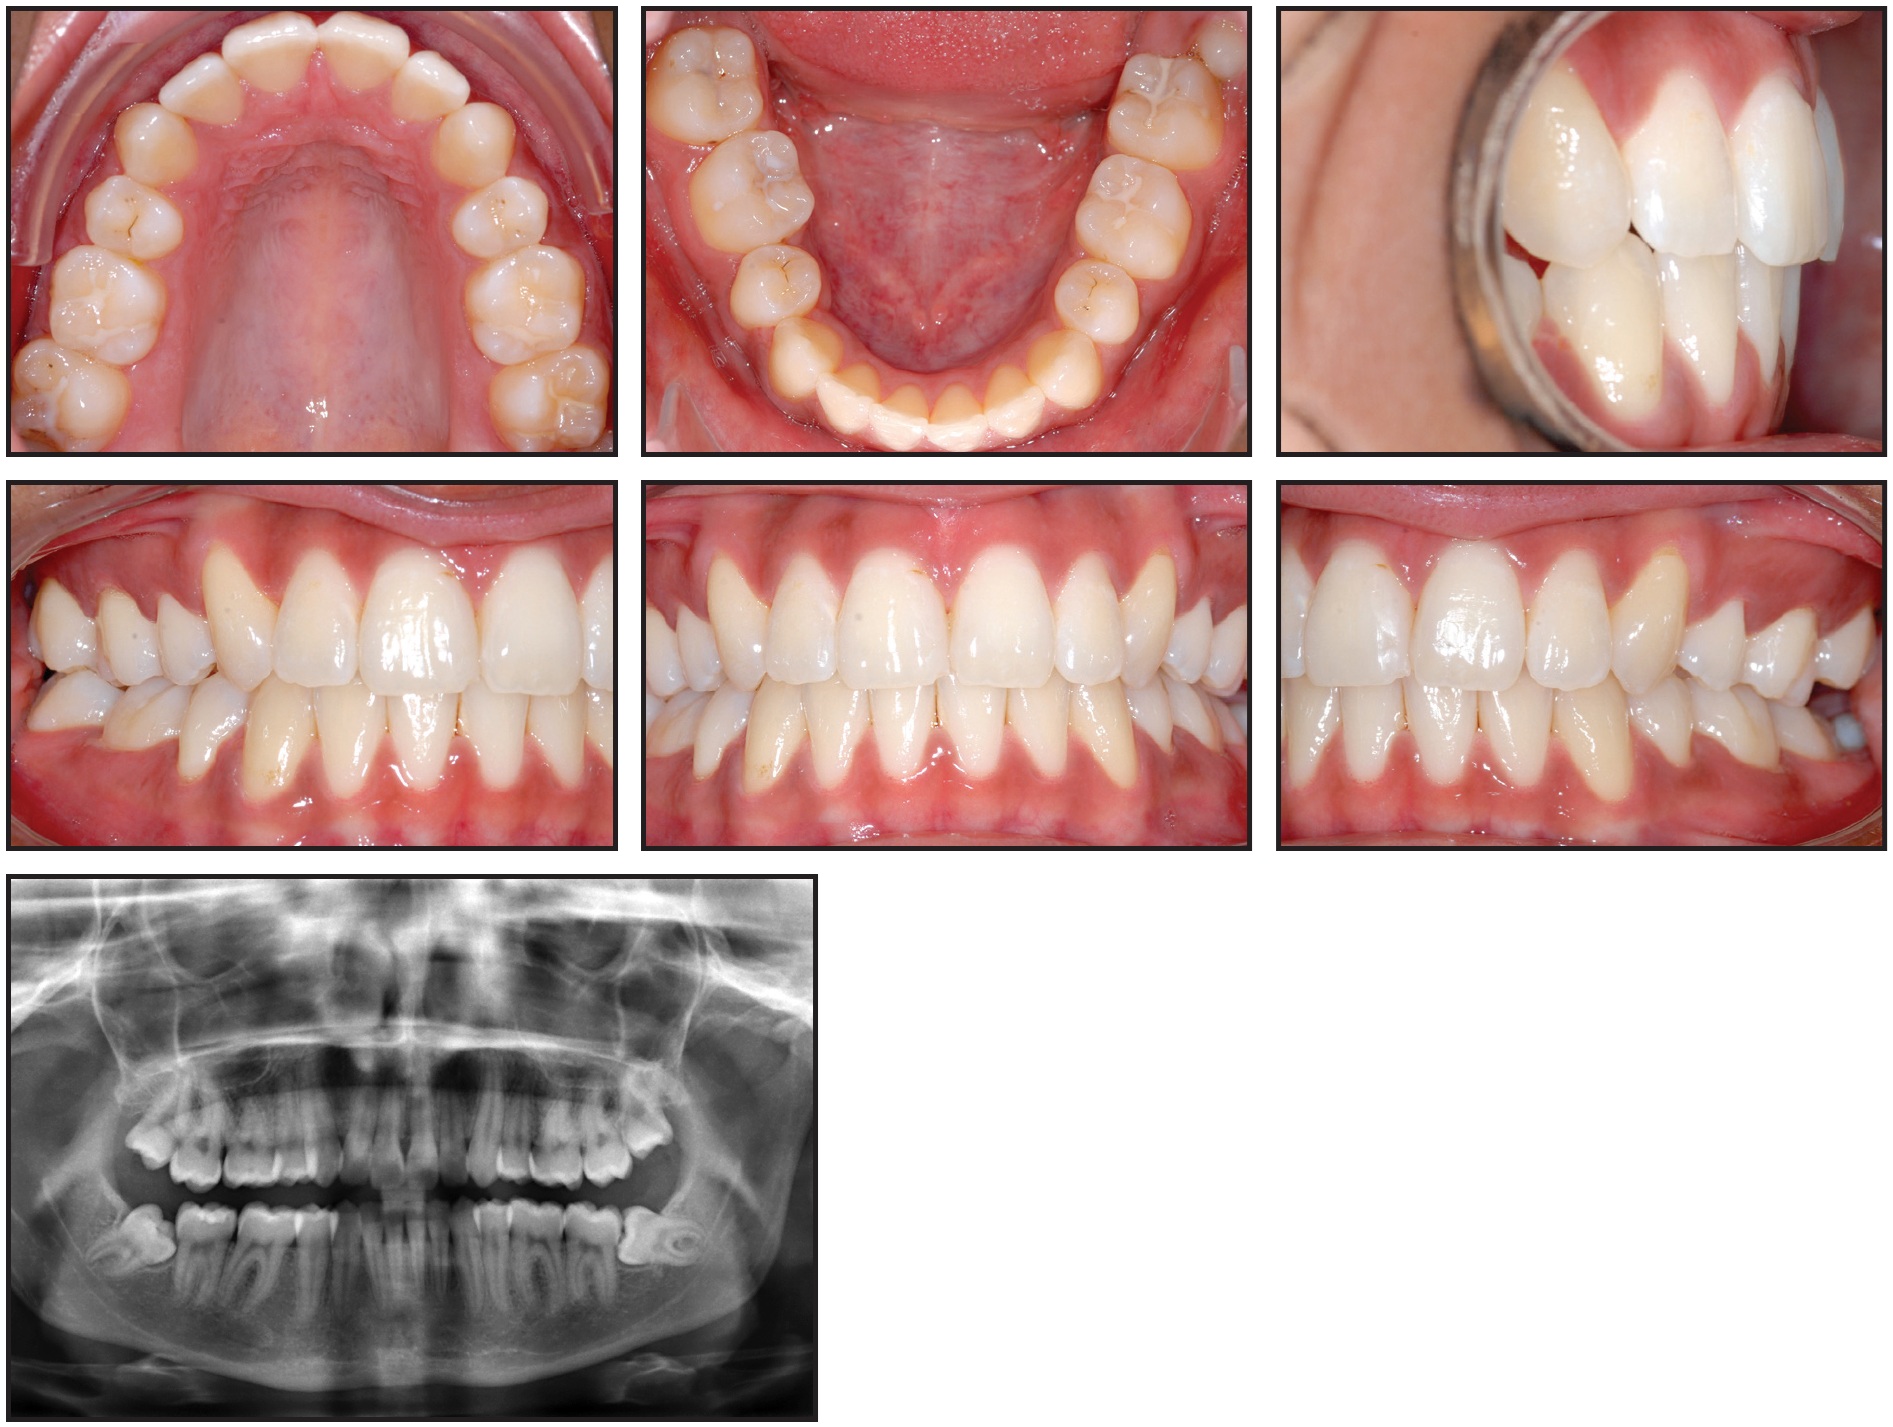

An 18-year-old female had previously undergone orthodontic treatment involving the extraction of four first premolars due to crowding in both arches (Fig. 6).

Fig. 6 Case 2. 18-year-old female patient with mesially impacted lower third molars two years and 10 months after completion of previous orthodontic treatment, when all four first premolars were extracted.

Her treatment had finished two years and 10 months earlier. At the time of our evaluation, the patient's upper third molars had erupted, but the lower third molars were severely mesially impacted. Considering the available space, mini-implants were inserted between the roots of the first molar and second premolar on the right and the canine and lateral incisor on the left. Again, the mechanics described above were implemented (Fig. 7).

After two years of treatment, both lower molars were upright, and a stable occlusal relationship to the upper molars was achieved (Fig. 8).

Fig. 8 Case 2. After two years of uprighting, showing good angulation and positioning of lower third molars.